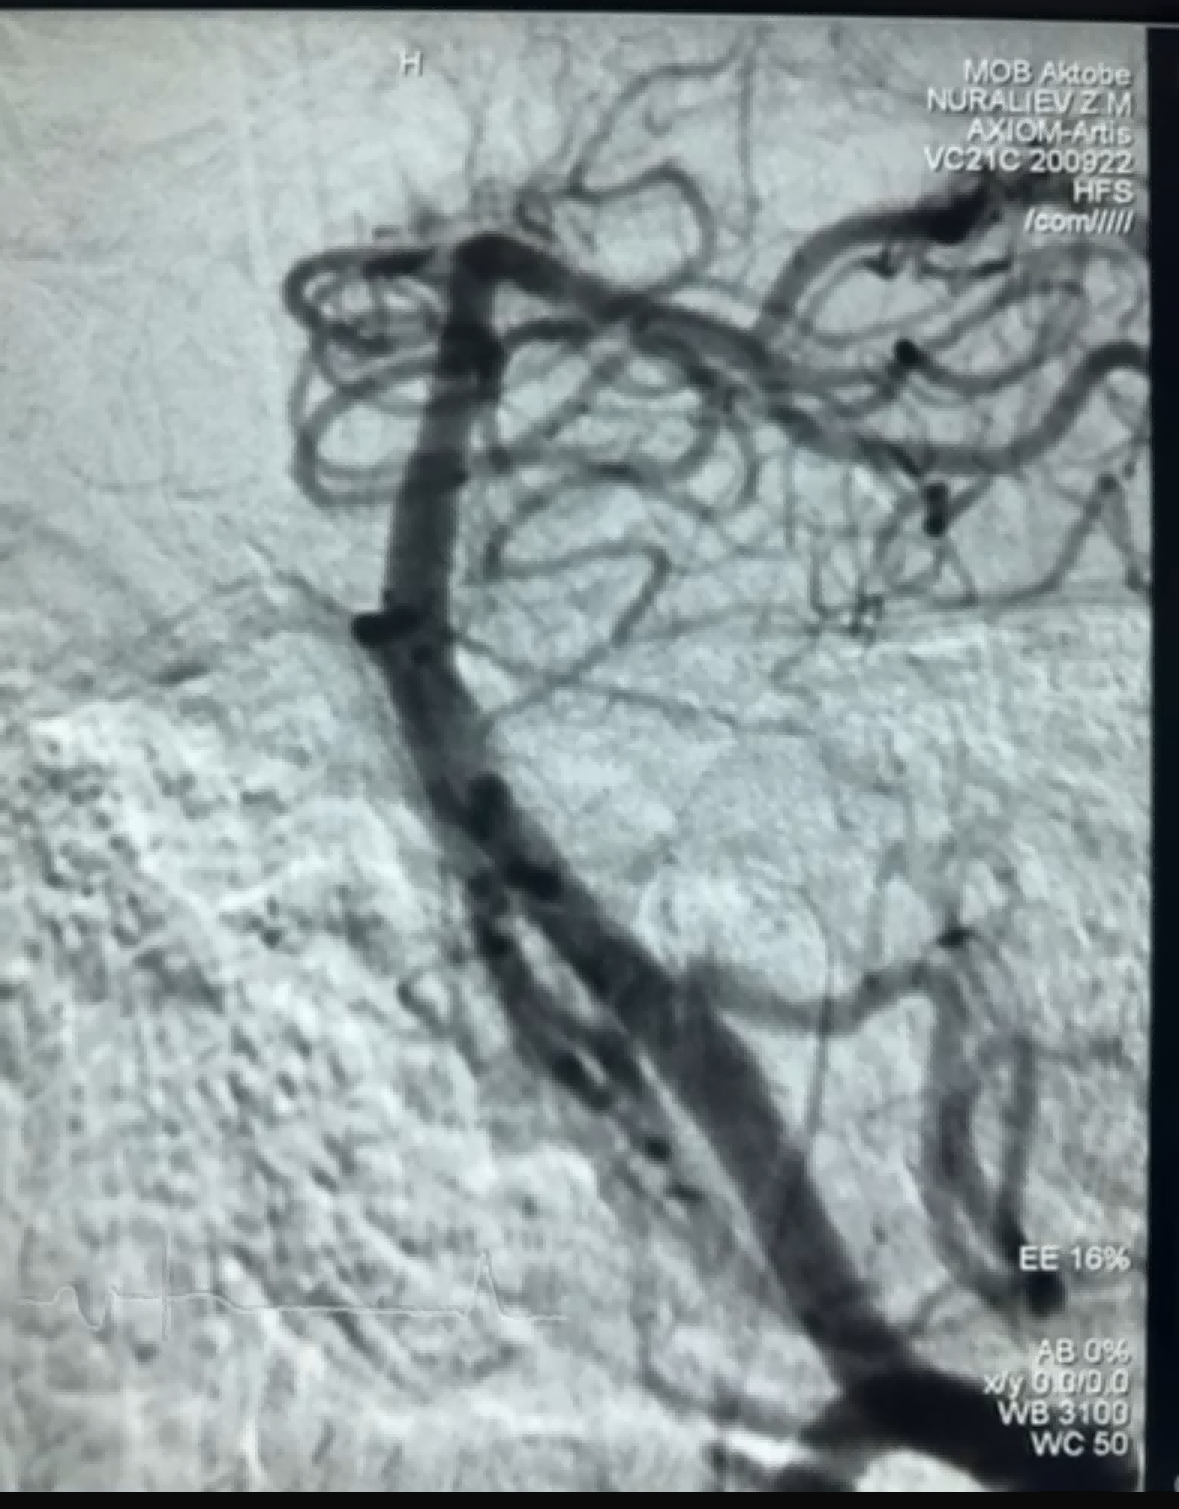

Yn ddiweddar, bu achos thrombectomi llwyddiannus gan ddefnyddio'r Dredger Stent Retriever o NeuroSafe Medical Co, Ltd Mae gan y Dredger Stent Retriever domen meddal an-ymledol, sy'n lleihau'r risg o ddifrod mewnlifol yn fawr, ac mae ganddo dwll siâp arbennig unigryw dyluniad sy'n dal clotiau gwaed yn bennaf trwy glampio'r newidiadau bwlch.